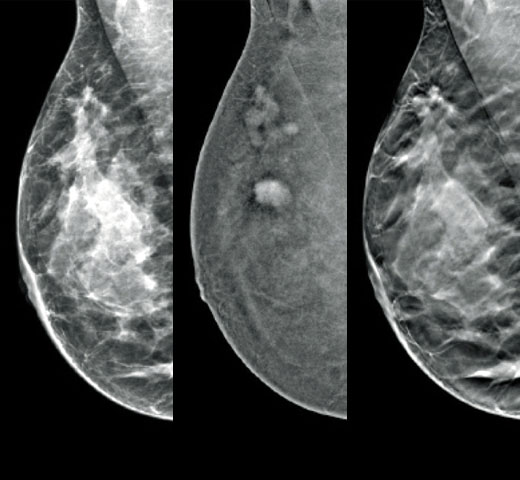

Sabemos que una densidad mamaria alta aumenta el riesgo de cáncer de mama en mujeres.1 Por tanto, es fundamental realizar un análisis preciso y sin sesgo. El software de la tecnología Quantra, basado en aprendizaje automático, analiza las imágenes 2D™ y de tomosíntesis para determinar la distribución y la textura del tejido parenquimatoso. Clasifica las mamas en cuatro categorías de composición mamaria de acuerdo con las directrices del Atlas BI-RADS (5.ª edición) del American College of Radiology (ACR).2

Además del volumen, el patrón y la textura del tejido fibroglandular pueden ser igualmente decisivos para la predicción mamográfica del riesgo de cáncer.3-5 ​​Mediante el análisis y la clasificación de la textura y el patrón de la mama, nuestra tecnología puede ofrecer la información precisa que necesita para realizar una clasificación más fiable y completa y, de este modo, diseñar con seguridad una vía de detección específica para cada paciente.

El algoritmo de aprendizaje automático objetivo asigna una categoría de densidad de mama de acuerdo con los patrones y la textura del tejido de la mama.

* Las clasificaciones se basan en las categorías BI-RADS del ACR, de acuerdo con las directrices revisadas publicadas en el Atlas BI-RADS (5.ª edición) del American College of Radiation (ACR). Estas directrices tienen en cuenta el patrón y la textura, y no solo el volumen, a la hora de determinar la densidad.